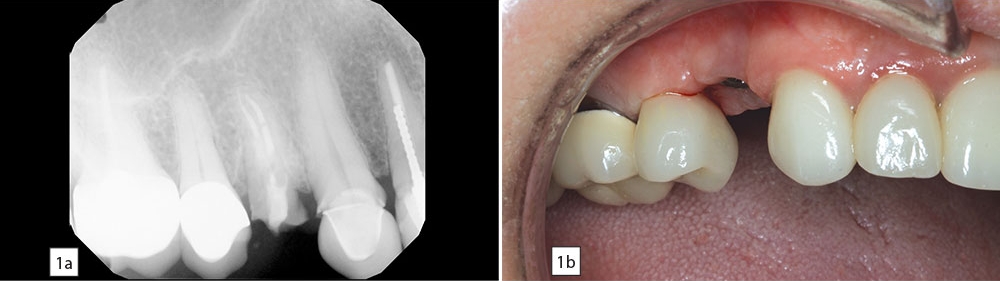

Figures 1a, 1b: Dr. Philip Gordon’s first Hahn Tapered Implant case, a maxillary premolar required extraction due to fracture. Four months later, an implant was placed into the healed extraction site.

PG: It was about two years ago for a patient who needed to replace a maxillary first bicuspid. This patient had a failing root canal and was not willing to cut down a canine and another premolar to have a bridge placed. So this was an ideal site for an implant. It’s actually a good area for beginners to place implants because you’re out of the zone of the maxillary sinus and you’re not near any major nerves. I extracted the tooth, did a site preservation graft, came back four months later and placed the Hahn implant. Four months after that, we came back and restored the implant with a screw-retained crown, and the patient is doing great. This was a soft bone area, and the aggressive threads allowed me to get great primary stability.